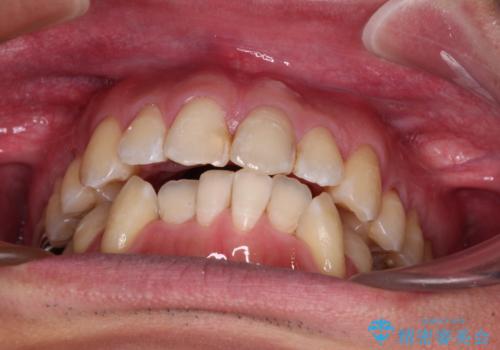

- 前歯のデコボコを気にして来院された患者様です。

下顎前歯のデコボコが特に強く、治療を早く終えることを考えるとワイヤー装置がお勧めですが、ワイヤー装置の異物感は避けたいのでインビザラインを希望されていました。

インビザラインで治療を行うか、ワイヤーで治療を行うかずっと悩んでいらっしゃいましたが、早く終わらせることを優先してワイヤー装置にて治療を行うこととしました。